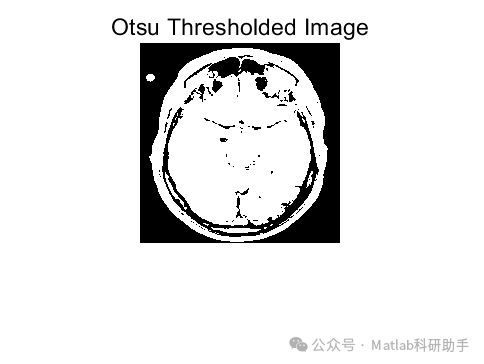

⛳️ 运行结果